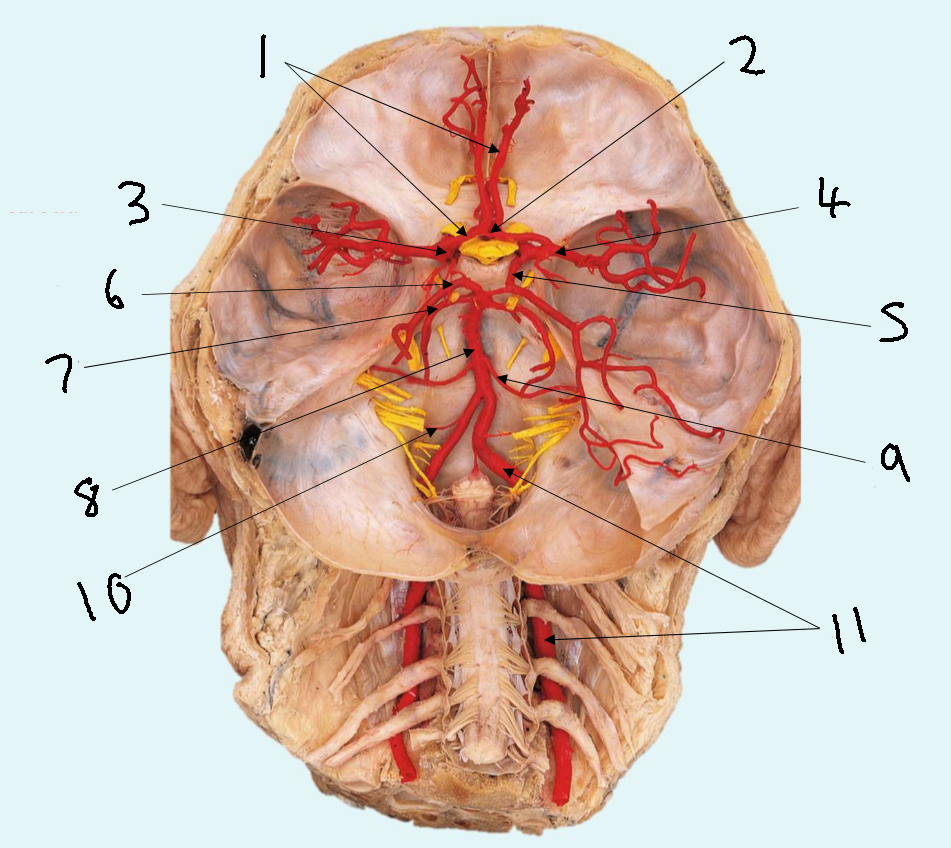

What is 1?

anterior communicating artery

What is 2?

anterior cerebral artery

What is 3?

middle cerebral artery

What is 4?

internal carotid artery

What is 5?

posterior communicating artery

What is 6?

posterior cerebral artery

What is 7?

superior cerebellar artery

What is 8?

pontine arteries

What is 9?

basilar artery

What is 10?

anterior inferior cerebellar artery

What is 11?

vertebral artery

What is 12?

posterior inferior cerebellar artery